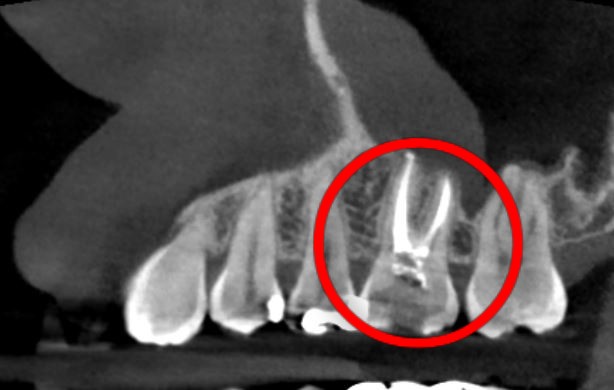

そのため、抜髄処置と感染した神経の管の中を綺麗にしていく根管治療をしました。

その後、Er:YAGレーザーを使用して根管内を殺菌した後に根管充填。

ファイバーコアを入れて支台築造をして仮歯を入れました。